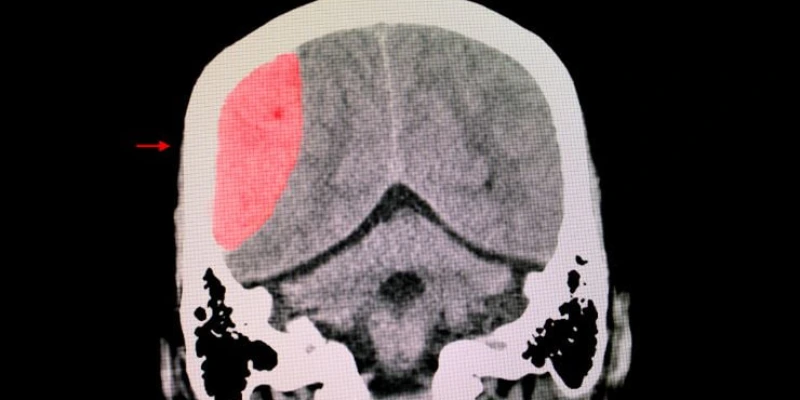

The human brain is, unfortunately, susceptible to many types of traumatic injuries. When any type of brain injury occurs, the victim is likely to suffer a host of short and long-term medical complications, and there is always a possibility for a brain injury to result in some type of permanent harm. Therefore, if you or a loved one recently suffered a brain injury of any kind, it’s vital to understand not only the medical complications you could face but also the potential legal proceedings you may need to navigate the secure compensation from a party responsible for the injury.

Treating brain injuries can be very difficult due to the unpredictable nature of these injuries. A seemingly mild brain injury can potentially result in life-changing permanent disabilities for the victim, while a seemingly severe brain injury may result in minimal long-term damage to the victim. Generally, there are three types of symptoms that any brain injury can cause.